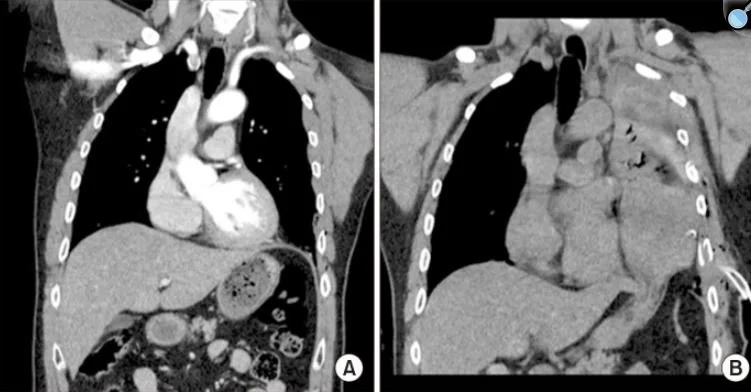

Case of a young male who fell off a bike. the L is the initial ct, the R is the next day after a chest tube.

a traumatic diaphragmatic hernia